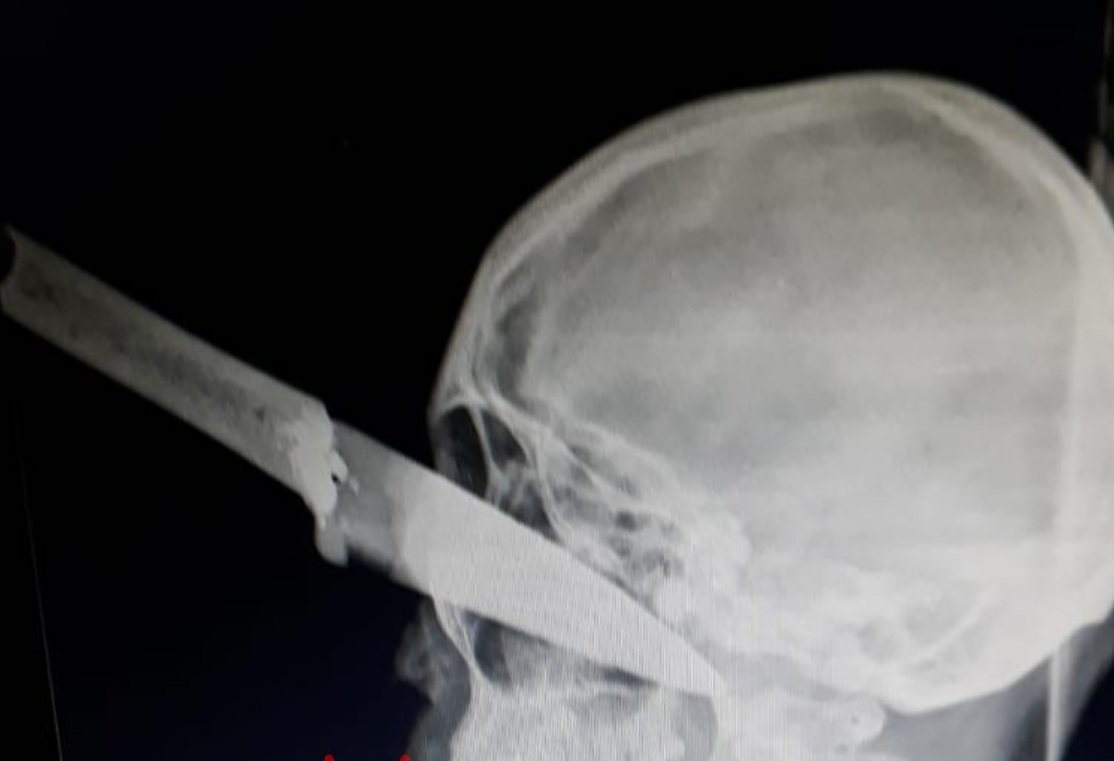

Máxima crueldad: la joven atacada con un cuchillo lucha por su vida

La joven atacada con un cuchillo por otra mujer, lucha por su vida y su estado es crítico, según indicaron fuentes a este medio. El arma con la que fue atacada le atravesó gran parte del frente del rostro.

La joven fue derivada a Salta donde tratan de salvarle la vida el hospital San Bernardo dónde se está realizando una compleja cirugía para extraer el cuchillo. Hay cuatro personas detenidas que quedaron a disposición de la Justicia.